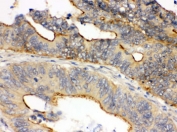

IHC testing of FFPE human intestinal cancer tissue with OSM antibody. HIER: Boil the paraffin sections in pH 6, 10mM citrate buffer for 20 minutes and allow to cool prior to staining.